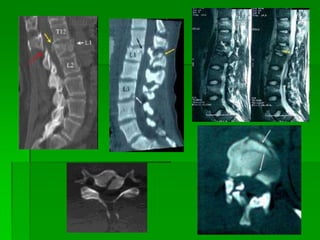

FRATURA COM LUXAÇÃO

COMPLETA – TORÁCICA BAIXA

Mecanismo de Trauma Raqui-Medularsem fratura  Extrusão de disco – Vetor de força axial. Queda vertical de pé ou sobre gluteos  Clínica – Secção de medula  Sub-luxação – Grau variável. Geralmente sem lesão medular grave  Luxação completa – rara, por ruptura ligamentar, Instabilidade, grave déficit medular apesar dos ossos já terem retornado ao lugar

• 26.

FRATURA COM LUXAÇÃO COMPLETA– TORÁCICA BAIXA